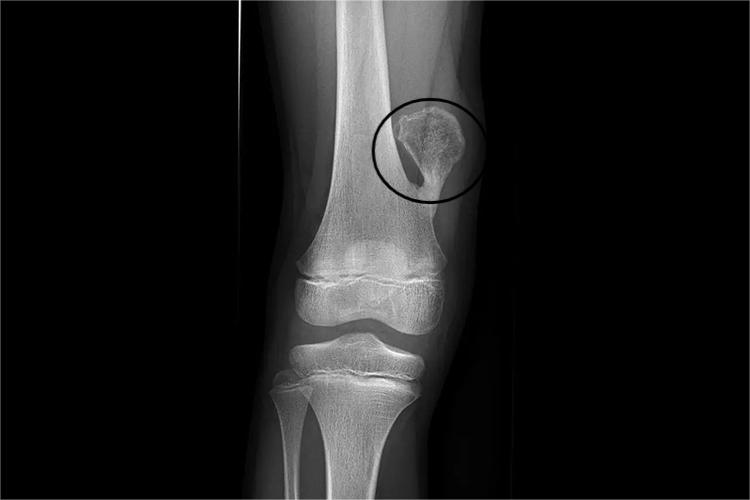

骨软骨瘤是位于骨表面的骨性突起物,顶面有软骨帽,中间有髓腔。患者可长期无症状,会出现骨性包块,若肿瘤压迫周围组织或其表面的滑囊发生炎症,则可产生疼痛、局部麻木、活动受限等。X线可在干骺端见从皮质突向软组织的骨性突起。